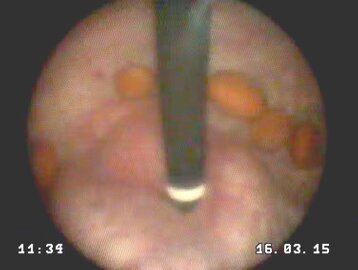

una carrellata di immagini per dare l'idea di cosa è possibile vedere con questo esame

visti in retrovisione con lo strumento flessibile

può provocare dolore ed ematuria